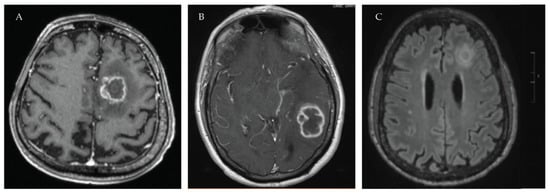

- Lionakis, M.S.; Dunleavy, K.; Roschewski, M.; Widemann, B.C.; Butman, J.A.; Schmitz, R.; Yang, Y.; Cole, D.E.; Melani, C.; Higham, C.S.; et al. Inhibition of B Cell Receptor Signaling by Ibrutinib in Primary CNS Lymphoma. Cancer Cell 2017, 31, 833–843.e5. [Google Scholar] [CrossRef]

- Ghez, D.; Calleja, A.; Protin, C.; Baron, M.; Ledoux, M.P.; Damaj, G.; Dupont, M.; Dreyfus, B.; Ferrant, E.; Herbaux, C.; et al. Early-onset invasive aspergillosis and other fungal infections in patients treated with ibrutinib. Blood 2018, 131, 1955–1959. [Google Scholar] [CrossRef]

- Alkharabsheh, O.; Alsayed, A.; Morlote, D.; Mehta, A. Cerebral Invasive Aspergillosis in a Case of Chronic Lymphocytic Leukemia with Bruton Tyrosine Kinase Inhibitor. Curr. Oncol. 2021, 28, 837–841. [Google Scholar] [CrossRef] [PubMed]

| BTK | PCNSL | Lionakis et al. | [63] | IFI incidence 44%; 7 cases of IA including 2 involving CNS; 1 PJP |

| CLL NHL | Ghez et al. | [65] | 33 cases of IFI amongst 16 centers over 4 years; 27 cases IA with 11 involving CNS; 4 cryptococcosis; 1 PJP | |